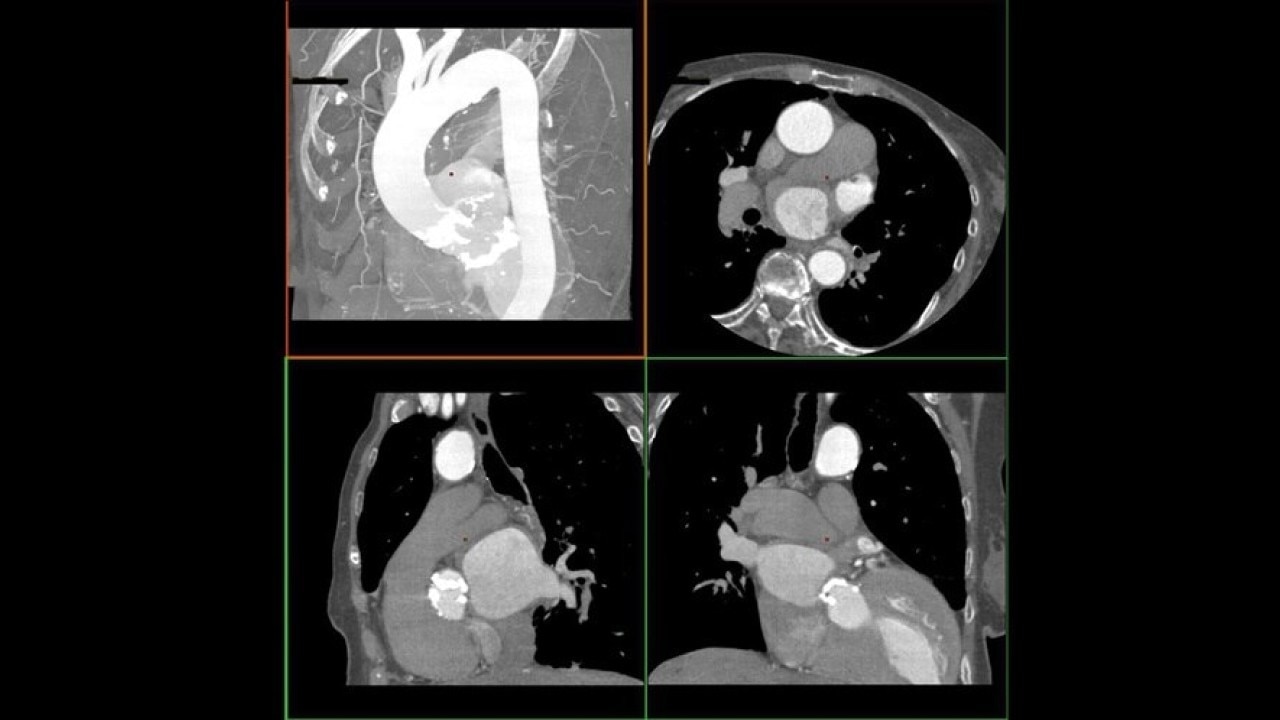

The Valve Planning protocol in the VesselIQ Xpress application lets you visualize cardiac anatomy with the degree of detail required to evaluate the presentation of the aortic valve. Armed with this information, you can develop a pre-procedural TAVR/TAVI plan to establish a therapy strategy for the patient.